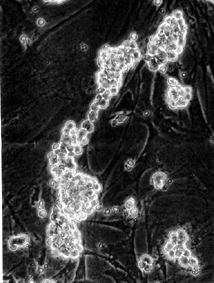

培養される精子幹細胞の様子